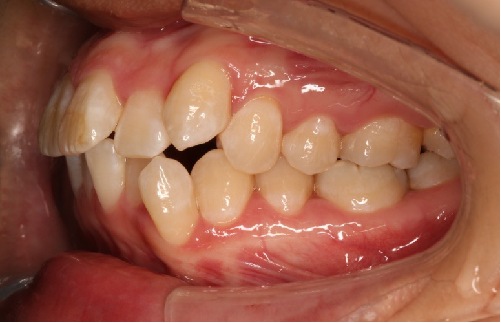

• 磨牙,尖牙I类关系,中线齐

• 上下牙列中度拥挤

• 上下前牙唇倾

IntraoralExamination(2016-08.31,Wu)